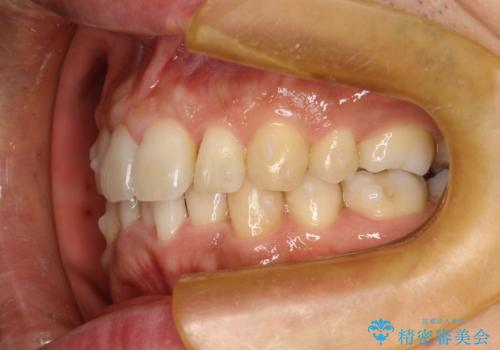

- 以前、上下左右4本抜いてワイヤー矯正をしていた方で、後戻りで下の前歯のガタガタを気にして来院されました。

マウスピース矯正にて、下の歯はIPR(歯と歯の間を削る)を入れることでガタガタの改善、咬み合わせの深さも改善をはかる治療計画をたてました。

歯と歯の間を削って隙間を作って矯正をしています。